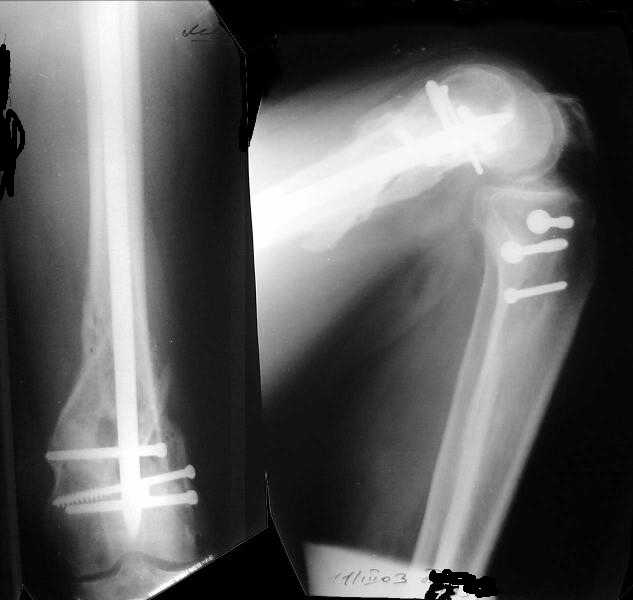

I attached an example of C2 fracture with result of the same technique in 5 months.

The mobilisation of knee is started immediately from the second day. Weight bearing is permitted as in any other interlocked nailing. That is, Toe touch to start with and within four days, partial to in another two weeks, full weight bearing. Of course that is assuming that the correct size nail has been used. Up to 70 kg body weight, 11no will be good enough and 12mm if more.Usually at the 1st followup, at 6 weeks time, they have full flexion..I

Enclosing a recent intraop picture